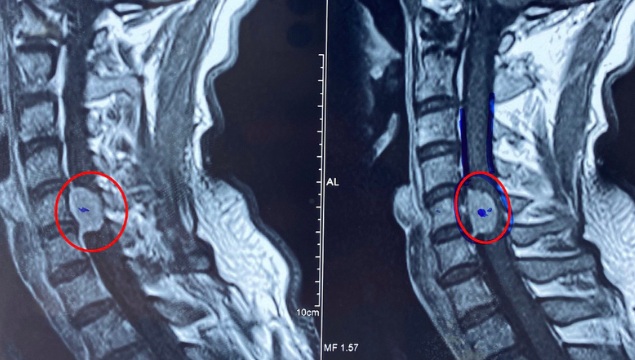

Bệnh nhân được chỉ định chụp cộng hưởng từ qua đó phát hiện khối u nằm trong tủy sống. Đây là một trong những bệnh lý nguy hiểm, cần can thiệp sớm để tránh nguy cơ tổn thương tủy không thể hồi phục.

Bác sĩ cho biết loại u mà anh C. mắc phải thuộc nhóm u trong tủy, đây là u nguy hiểm nhất.

Để loại bỏ khối u, các bác sĩ phải thực hiện kỹ thuật phức tạp: Bổ đôi tủy sống để tiếp cận và cắt bỏ khối u. Phương pháp này đòi hỏi sự chuẩn xác tuyệt đối, vì tủy sống là cơ quan thần kinh trung ương, điều khiển mọi hoạt động vận động, cảm giác và chức năng nội tạng.

Trước khi phẫu thuật, anh C. được các bác sĩ tư vấn kỹ càng về nguy cơ cao, bao gồm mất chức năng vận động hoặc cảm giác và liệt hoàn toàn. Phẫu thuật cắt u trong tủy của anh C. rất khó vì u nằm trong tủy, u lớn, vị trí khối u gần trung tâm hô hấp, tuần hoàn, nguy cơ liệt, không thở được, tử vong cao.